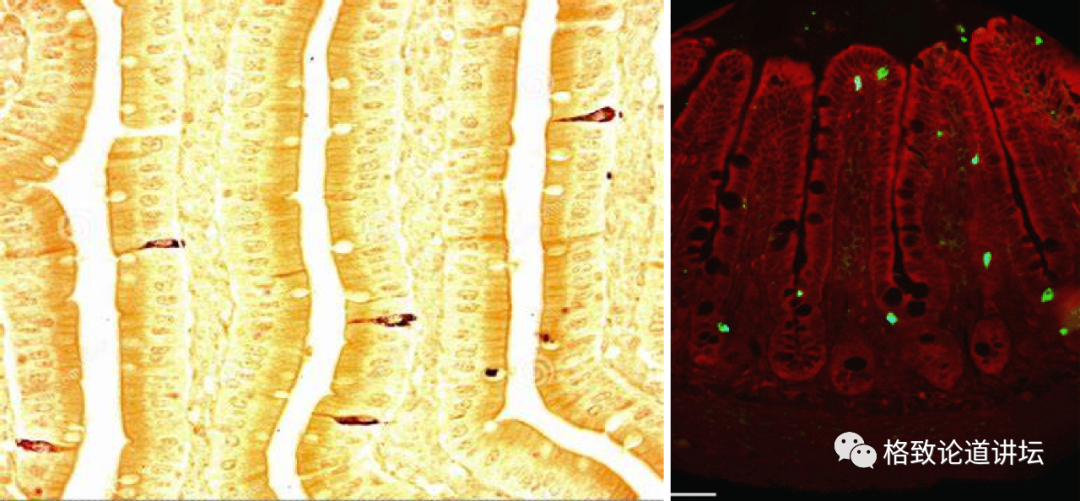

▲ 胃肠道和肠道内分泌细胞

这张图的右侧是我们的肠道黏膜上皮细胞。在这些肠道黏膜上,皮细胞之间还散在分布着很多成三角形样的特殊细胞,这些细胞是内分泌细胞,我们也叫它胃肠内分泌细胞。

在这张图里面,用棕色标记出来的,以及右侧用绿色荧光标识出来的,都是散在分布的内分泌细胞。

大家可以看到,它数量好像不是很多,但是因为我们胃肠道黏膜的面积非常大,所以在胃肠道分布的内分泌细胞,实际上它的数量是非常巨大的,而且种类非常多。